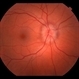

- optic nerve edema

Fundus camera

Topcon - Description